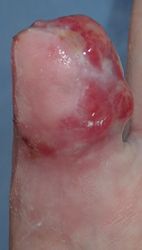

30歳男。東京都八丈島

2014年12月29日,ワイヤーに左示指を巻き込まれて不全切断受傷。〇〇病院を受診し,直ちに△△病院に救急ヘリ搬送され,形成外科で緊急手術(再接着術)となったが,生着せず,手掌部で切断⇒断端形成の予定だったが,患者の叔母(東京在住)がカンボジアで湿潤治療をしているKEN CLINICの奥澤先生と知り合いだったため,当科で一度診てもらったほうがいいとアドバイスされ,セカンドオピニオンで当科を受診。

当初はラップで被覆(ワイヤーのためにプラスモイストではうまく覆えなかった)。1月21日,22日にワイヤー抜去。3月に入ってから突出した骨を骨鉗子で切除(無麻酔で大丈夫だった)。3月19日,八丈島に戻った。